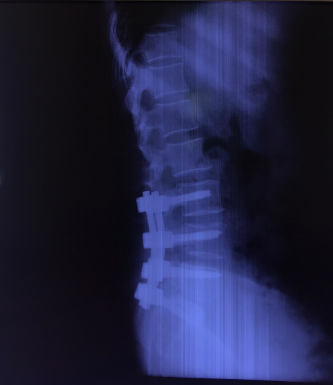

Hình ảnh: X Quang bệnh nhân sau phẫu thuật hàn xương, nắn chỉnh cột sống